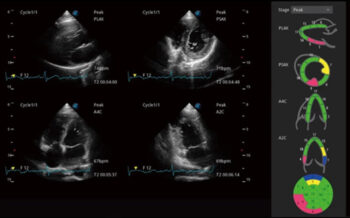

Stress echo

Эмч нарт амарч байхдаа болон дасгал хийсний дараа олон динамик зураг авч, тэдгээрийг зэрэгцүүлэн харьцуулах энгийн загвар. Зүрхний булчингийн амьдрах чадварыг илүү үр дүнтэй үнэлэхийн тулд хананы хөдөлгөөний мэргэжлийн оноо, тайланг өгдөг.

Миокардийн тоон шинжилгээ (MQA)

Миокардийн механикийн нарийн тоон хэмжилтийг MQA-ээр дамжуулан хийдэг бөгөөд энэ нь хананы хөдөлгөөнийг бодит цагийн мэдрэмжтэй хянахад үндэслэдэг. Энэ нь деформаци, деформаци, шилжилт хөдөлгөөн, хурд гэх мэт үнэлгээг өгдөг.